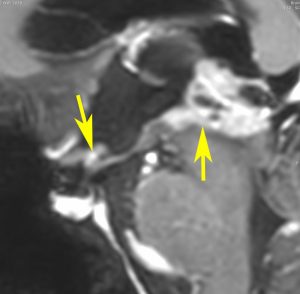

放射線が外れやすい部位は再発源となります

側脳室先端(前角,後角,側頭角,閂),下垂体と大脳基底核に放射線が入らないとその部位から再発します。

再発ジャーミノーマの画像です。延髄背側の閂 ovexという部位に再発しています。

このパターンはとても多いです。なぜかというと,全脳室照射の時に,第4脳室下端のovexの上衣 ependyum を照射野に入れない放射線治療医の先生がいるからです。放射線科の先生にもちょっとした知識が必要なのです。

これは再治療で腫瘍が消えても不可逆的な重症の延髄障害を残してしまいます。